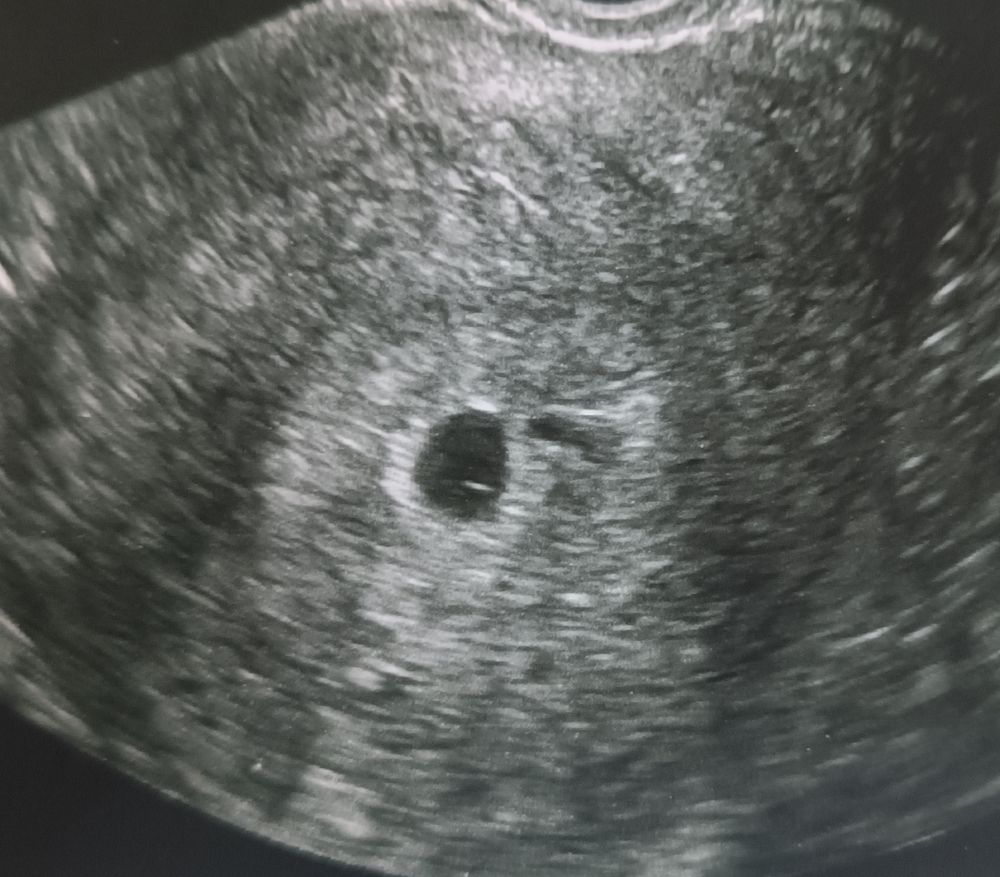

Светик,

Смотрите, сверху вниз. 5 недель, 6 недель, 8 недель. Как тут не увидеть?))